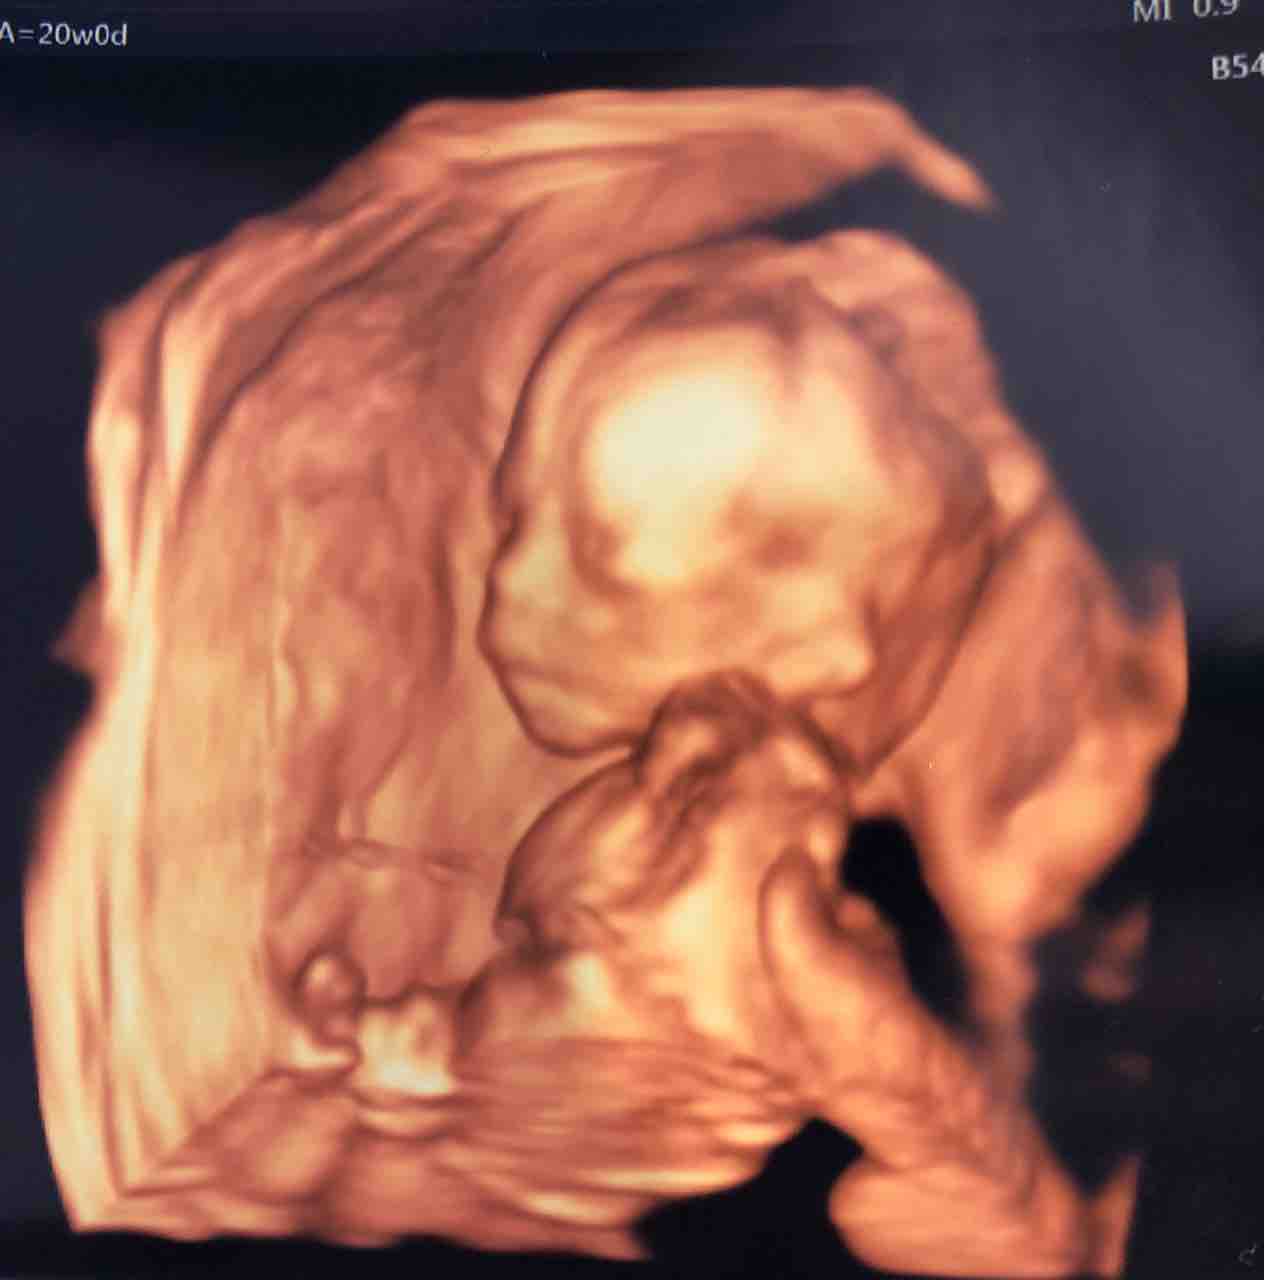

22w 赤ちゃん-1/8/19 妊娠22週の赤ちゃんの基礎情報 身長、体重、発達 妊娠22週は妊娠6ヶ月の第3週にあたります。 赤ちゃんの平均的な重さは500g程度になり、骨格や筋肉もかなりしっかりしてきます。 また、このころから赤ちゃんのまぶたが上下に分かれ始め、まばたきをするようになります。 妊娠22週目に胎動を感じるママも! 逆子は気にしなくても大丈夫 お腹の中でより激しく動き回るようになるた24/3/17 22週3日で447gの赤ちゃんを出産。 一度きりの不妊治療で授かった我が子が起こした奇跡 妊娠・出産 不安やリスク 早産 妊娠中期 妊娠6ヶ月 妊娠22週 編集部 Tweet 不妊治療をすることになった私は、最初から「体外受精」で治療をしてくださいとお

わたしの赤ちゃんは今日のエコーで見ると287。 体重は約360g。 22週5日の平均よりもかなり小さいと。 先生いわく 大人になると、身長180cmの人もいれば160cmの人もいるけど 小学校1年生の時点ではみんなそう変わりはないと。 この±15の間に入らないといけずいぶん赤ちゃんらしくなってきました。 妊娠22週:性腺が発達、ホルモン分泌も始まる 妊娠22週0日の胎児の大きさ/体重3g~617g(*) 男の子は精巣、女の子は卵巣のことを、性腺(せいせん)といいます。 妊娠22週ごろになると、性腺はこれまで以上に発達してきます。 とくに、男の子の精巣からはテストステロン(男性ホルモン)が大量に分泌されるようになります。 このテストステ17/6/21 妊娠22週の赤ちゃんの体重は400~500gほどです(※4)。 赤ちゃんの成長速度は加速し、ここから4週間で体重は今の2倍近くまで増えます。 これは体が大きくなるだけではなく、臓器が成長して重くなったり、体の周りに脂肪がついたりすることが要因です。 ただし、胎児の成長スピードには個人差があります。 体重はあくまでも目安と考えましょう。 またこの時期は、聴覚や嗅覚、

60円 ピエール ルイ マシア PierreLoui Mascia グレーホワイト ゼブラ スパンコール カシミアレーヨン薄手1枚仕立てストール 国内正規品 メンズ Men's,オフィスチェアカバー 椅子カバー チェアカバー DauStage 厚手 伸縮素材 選べる 6色 マイクロファイバークロス付き (08、ブラウン2,タンガロイ妊娠22週胎児体重は正常発育児の954%が3g~617g 平均体重:469gとなります。 ※1 22週目を過ぎるとへその緒が太くなり、赤ちゃんによりスムーズに栄養が運ばれるようになります。 ますますしっかりとした在感を示すようになってきます。 ハッキリとした胎動を感じられるようになり、喜ぶ妊婦さんも多いです。 妊娠中期に入る頃には、すべての妊婦さんが胎動を感じられるようになりま10/8/16 こんにちは、黒川あさひです。 妊娠6か月目に突入した先日、検診に行ってきました。 そして、赤ちゃんの性別が判明しました。 結果は男の子でした! 自分が男の子の母親になるという実感はあまりわかないのですが、何にせよ元気に育ってくれたらいいなあと思います。